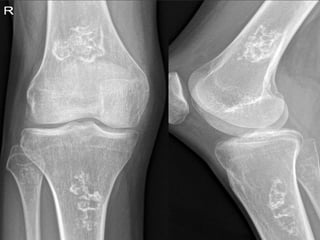

Most common sites

 Femur condyles

X-ray of head of femur (AVN)

 Crescent Sign

 Snowcapping

 Areas of lucency

 Flattening of joint surface

Crescent Sign

Luscent areas

Flattening of joint

surface

Snowcapping

Flattening

X-ray of headof femur (AVN)  Crescent Sign  Snowcapping  Areas of lucency  Flattening of joint surface